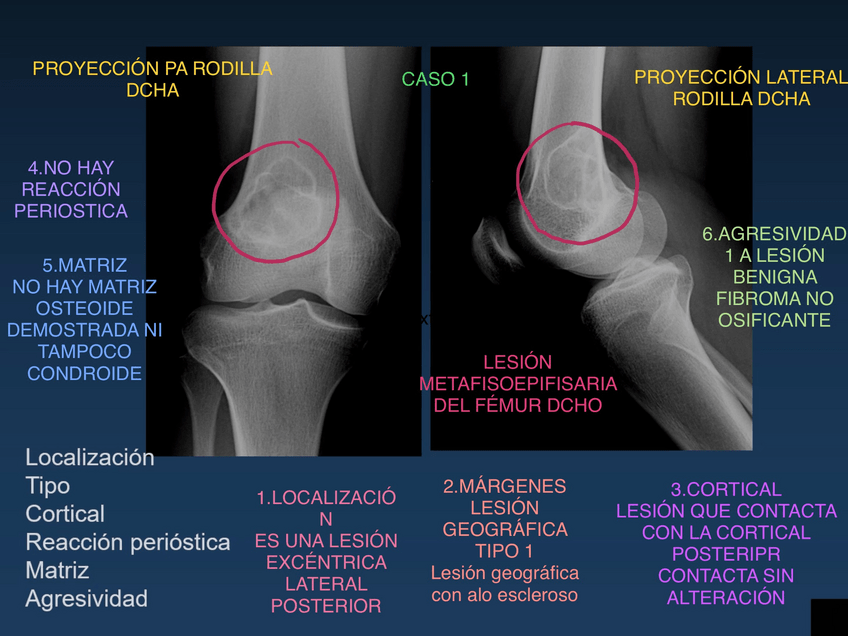

Soluciones de la 2ª práctica de musculoesquelético del curso 25-26